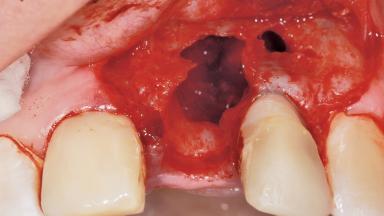

A 36-year-old female patient was referred for the replacement of the upper left central incisor (tooth 21), which had fractured. Although the tooth had been asymptomatic for many years, the crown began to loosen, at which time she presented to her dentist for an assessment. Teeth 21 and 22 had both been endodontically treated many years previously. She was a healthy individual and a non-smoker.

The crown of tooth 21 was splinted to the adjacent teeth with composite resin, and the gingiva was inflamed.